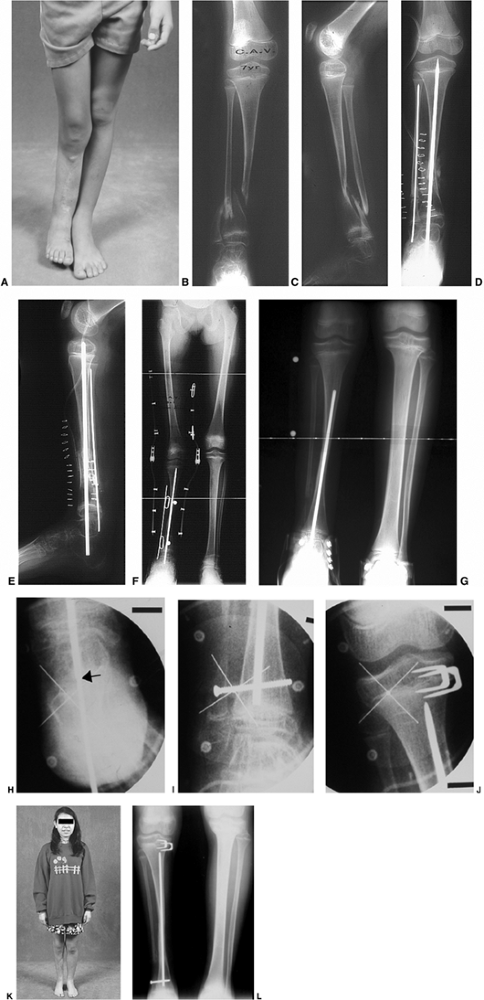

![]() |

Figure 28.20 A: Adolescent Blount disease frequently occurs in very large teenagers. The deformity is often bilateral. B:

Long cassette films are used to assess mechanical alignment as well as the anatomic axes of the femur and tibia. Distal femoral deformity is often present as well as proximal tibial varus. C: Procurvatum of the proximal tibia develops, with increased posterior slope of the proximal tibia. D: Distal tibial valgus develops to allow the foot to have flat contact with the floor. E: Restoration of normal alignment may include multilevel osteotomies. Preoperative templates are useful for planning operative strategies. F: In this example, the plan included immediate correction of distal femoral varus using a blade plate and gradual correction of proximal tibial varus and distal tibial valgus using a circular small wire frame. G: Multiplane correction is facilitated with this technique. Adjustments can also be made to correct the procurvatum that may be present. H: The circular frame provides flexibility. It also allows lengthening as needed in cases of unilateral or asymmetric deformity. I: Radiographs confirm the restoration of alignment. Correction is generally well maintained. J: Clinical photo after bilateral treatment shows satisfactory clinical correction compared to the preoperative photo. K: Correction of procurvatum restores normal orientation of the knee. |

extremities is essential for evaluating the patient with adolescent

tibia vara (Fig. 28.20B). Most adolescent

deformity is common, because that physis can also undergo excessive

loading (83,110,116) (Fig. 28.20 A,B,C).

This is in contradistinction to infantile tibia vara in which the

infantile tibia vara. The combination of varus, procurvatum, and

internal rotation results in a complex three-dimensional deformity of

the proximal tibia. As the proximal tibial and distal femoral varus

deformities increase, there is a significant strain placed on the

lateral collateral ligament of the knee, which leads to laxity and

varus deformity within the knee joint. In some very severe cases,

compensatory distal tibial valgus develops to allow the patient to

place the foot flat on the floor (Fig. 28.20D).